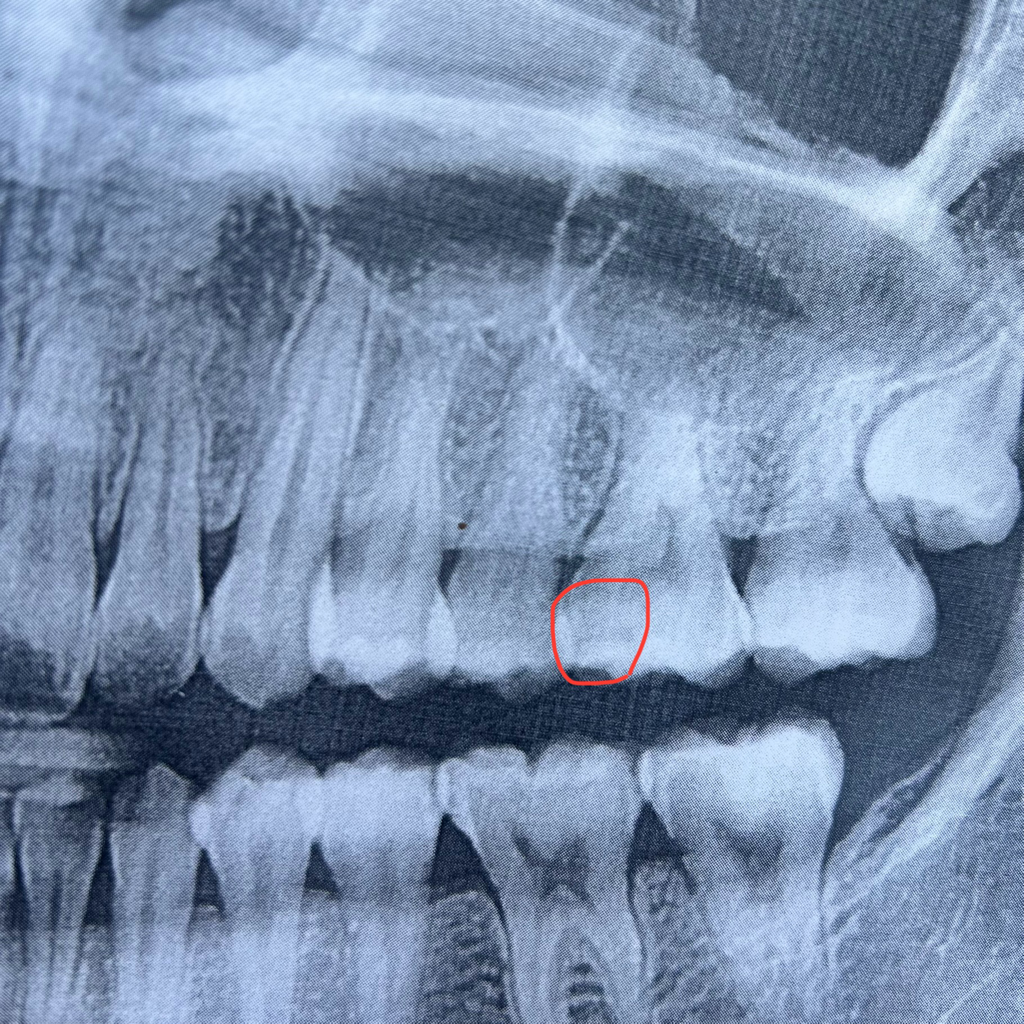

두 번째 치과에서는 이끼리 겹치게 사진을 찍으면

그렇게 보일 수 있으나

여기서는 안 겹치게 찍었고

여기서 찍은 사진 상으로는 그만한 충치는 없다

• 2번 째 사진

인접면 충치의 경우 인접한 두 치아가 겹치지 않게 사진을 찍어 확인하는 것이 맞습니다. 교익 방사선 사진이라고 합니다.

두번째 치과에서 찍은 교익 방사선 사진을 보면 특별히 엄청 큰 충치는 아닌 것으로 판단됩니다. 또한 인접면 충치의 경우 특히 음식물이 잘 끼는 증상이 있으니 증상으로도 체크가 가능합니다.